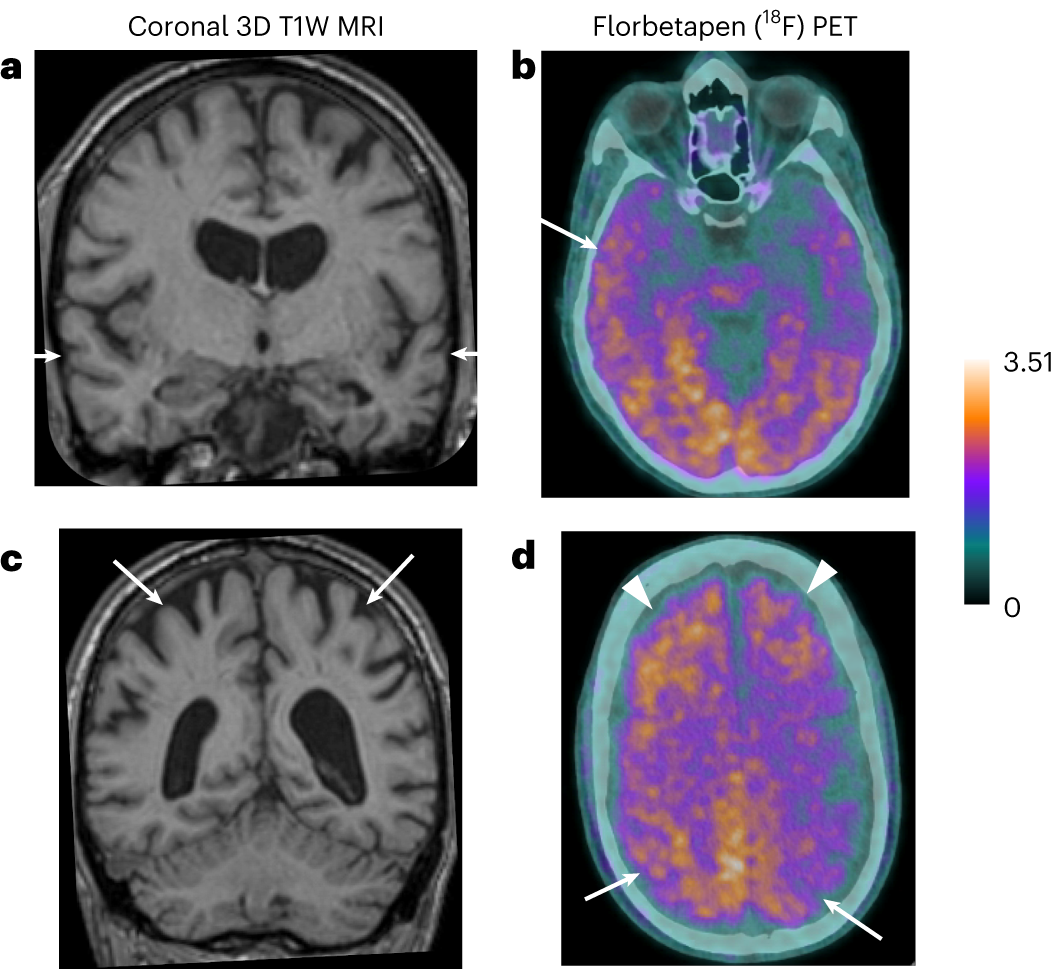

Fig. 1: Magnetic resonance and amyloid-PET (18F-Florbetapen) images—case 3.

a, High-resolution three-dimensional (3D) T1-weighted (T1W) magnetic resonance (MR) coronal image through the temporal lobes demonstrates volume loss within the temporal lobes bilaterally (arrows) and also marked central atrophy. b, Axial PET images demonstrate diffuse increased tracer uptake in the cortex and subcortical white matter, increased in the right temporal lobe compared to the left. c, High-resolution MR (3D T1W) coronal image through superior parietal lobules bilaterally demonstrates marked volume loss (arrows). d, Axial PET images demonstrate marked tracer uptake within the superior parietal lobules bilaterally (arrows) in addition to increased uptake in the bilateral frontal lobes (arrowheads).